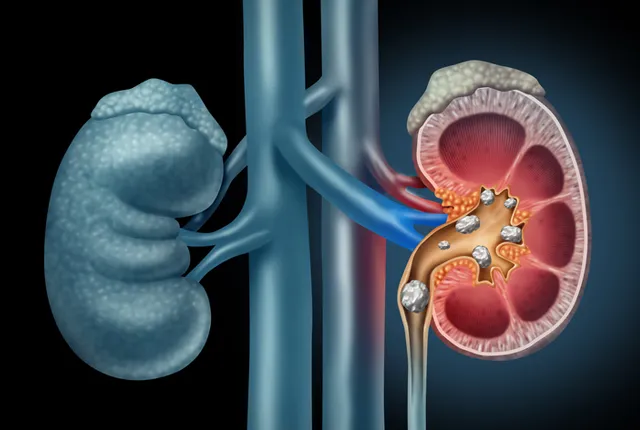

سونوگرافی کلیه (Renal Ultrasound) یک روش تصویربرداری پزشکی غیرتهاجمی است که با استفاده از امواج صوتی با فرکانس بالا، تصویری دقیق و زنده از کلیهها و ساختارهای اطراف آنها ارائه میدهد. در این روش هیچگونه اشعهای وجود ندارد و به همین دلیل، یکی از ایمنترین ابزارهای تشخیص برای تمام گروههای سنی، از نوزادان تا سالمندان محسوب میشود. در سونوگرافی کلیه، پزشک یا کارشناس تصویربرداری میتواند اندازه، شکل، موقعیت و وضعیت جریان خون در کلیهها را بررسی کرده و وجود مشکلاتی مانند سنگ کلیه، کیست، تورم، انسداد، تومور یا عفونت را تشخیص دهد. همچنین این روش برای ارزیابی کلیههای پیوندی یا بررسی علل نارسایی کلیه نیز کاربرد گستردهای دارد.

سونوگرافی کلیه برای بررسی وضعیت سلامت کلیهها و ساختارهای اطراف آن بهکار میرود. این روش به پزشکان کمک میکند تا بدون نیاز به جراحی یا پرتوهای مضر، تصویر دقیقی از اندازه، شکل، موقعیت، بافت کلیهها و جریان خون در آنها به دست آورند. یکی از مهمترین کاربردهای سونوگرافی کلیه، تشخیص سنگ کلیه است. این روش میتواند وجود سنگهای کوچک و بزرگ در کلیه یا مجاری ادراری را بهراحتی نشان دهد. برخی دیگر از کاربردهای سونوگرافی کلیه عبارتند از:

- تشخیص و بررسی سنگ کلیه: مشاهده سنگها و تعیین محل و اندازه آنها

- بررسی انسداد مجاری ادراری: مانند انسداد حالب یا مثانه

- ارزیابی اندازه، شکل و ساختار کلیه: جهت تشخیص تغییرات ناشی از بیماریهای مختلف مثل کلیه پلیکیستیک، تومورها یا کیستها

کلیهها معمولا در حدود ۱۰-۱۲ سانتیمتر طول دارند. کوچکتر یا بزرگتر بودن کلیهها میتواند نشانه مشکلاتی مثل مزمن شدن بیماری یا التهاب باشد. بررسی قشر کلیه و مدولا (بخشهای داخلی) برای تشخیص ناهنجاریهایی مثل کیست، توده، سنگ، یا التهاب در سونوگرافی توسط پزشک باید انجام شود. مشاهده هر نوع سنگ، رسوب، یا انسداد در مجاری ادراری یا لگنچه کلیه و بررسی وجود مایع غیرطبیعی یا تجمع آب اطراف کلیه که میتواند نشاندهنده عفونت یا التهاب باشد در سونوگرافی کلیه قابل تشخیص است و در صورت استفاده از سونوگرافی داپلر، جریان خون در کلیهها نیز مورد بررسی قرار خواهند گرفت.